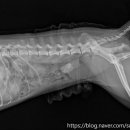

• 선부중앙동물의료센터 | 안산 고양이 이물 수술 전문 | 선부중앙동물의료센터 소화기 수술 후기 및 입원 관리

안녕하세요, 안산의 모든 반려가족분들! 선부중앙동물의료센터입니다. 🐾 고양이를 키우는 집사님들이라면 한 번쯤 '혹시 우리 아이가 이걸 먹은 건 아닐까?' 하는 걱정에 가슴이 철렁했던 적 있으실 거예요. 고양이는 호기심이 많고 혀의 돌기 때문에 이물질을 삼키기 쉬운 구조를 가지고 있거든요. 오늘은 소화기 이물...